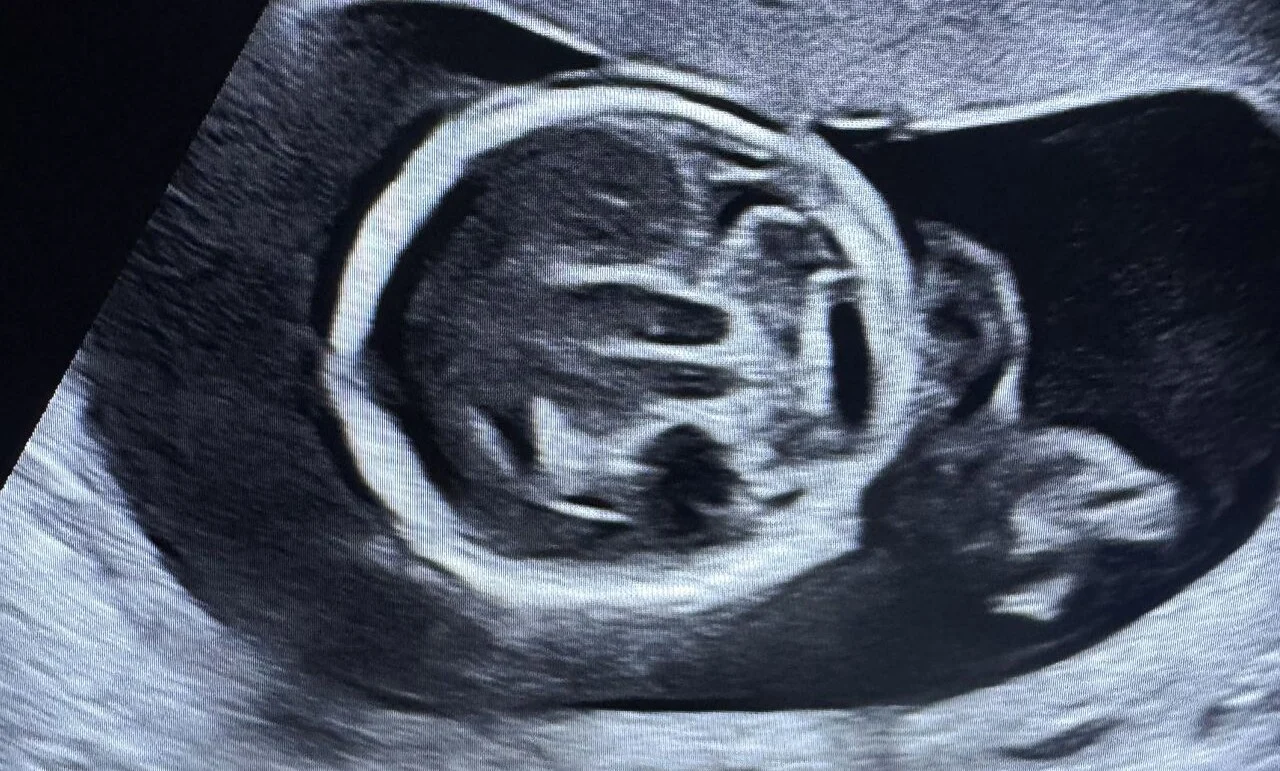

What is the Importance of Ultrasound During Pregnancy?

“What is the Importance of Ultrasound During Pregnancy?

1. Cardiac Activity Scan

A cardiac activity scan, typically conducted between 6-7 weeks of pregnancy, provides information about the duration of pregnancy by the length of the embryo – CRL. It also confirms whether the pregnancy is viable and live by detecting the presence and strength of a developing heartbeat.

2. First Trimester Scan

NT NB ultrasound or Level 1 ultrasounds look for Nuchal translucency, Nasal Bone with other structural and doppler parameters to ascertain with a Dual marker test that the developing fetus is healthy and doesn’t have any genetic syndrome like Down syndrome. Usually performed between 11 weeks to 14 weeks of pregnancy.

3. Level 2 Scan

A Level 2 ultrasound is performed between 18 to 22 weeks of pregnancy. Level 2 ultrasound is performed to produce images of the fetus and its internal organs. The ultrasound helps to assess the size and growth of the foetus, evaluate the formation of the brain, face, spine, heart, lungs, and other organs, and to identify any potential structural abnormalities.

In addition, the ultrasound can help determine the placenta’s position, evaluate the amount of amniotic fluid surrounding the fetus, and assess the blood flow in the umbilical cord.

3D ultrasound (and even 4D) is becoming more common and popular.

4. Fetal Echo Scan

A fetal echo scan is an ultrasound test used to examine the heart of a developing fetus. Fetal echo scans are typically performed between 19 and 22 weeks of pregnancy and are commonly used to diagnose heart problems in the fetus.

Fetal echo scans are important because early detection and treatment of heart problems in the fetus can significantly improve outcomes for both the mother and the baby.

Doppler and Growth Scans

A growth scan is typically conducted in the third trimester of pregnancy to evaluate the developing fetus’s growth and well-being. This scan assesses various parameters such as the fetal size, weight, and the amount of amniotic fluid present in the womb. Generally, the first growth scan is done at around 28 weeks, and further scans, if needed, are decided based on the first scan’s findings. If everything appears normal, a second growth scan is typically performed around 36 weeks, which is often combined with a Doppler scan.A Doppler scan measures the blood flow through the umbilical cord and different parts of the fetal body, such as the fetal brain and liver. This scan can indicate whether the fetus receives enough oxygen and nutrients through the placenta.

Conclusion!

Ultrasound plays a crucial role in pregnancy, providing valuable information about the growth and development of the fetus, placenta, and surrounding structures. Whether it is transabdominal ultrasound or 3-D, from observing blood flow and detecting abnormalities, ultrasound is a powerful tool for expectant parents and healthcare providers to produce detailed images of the baby.”